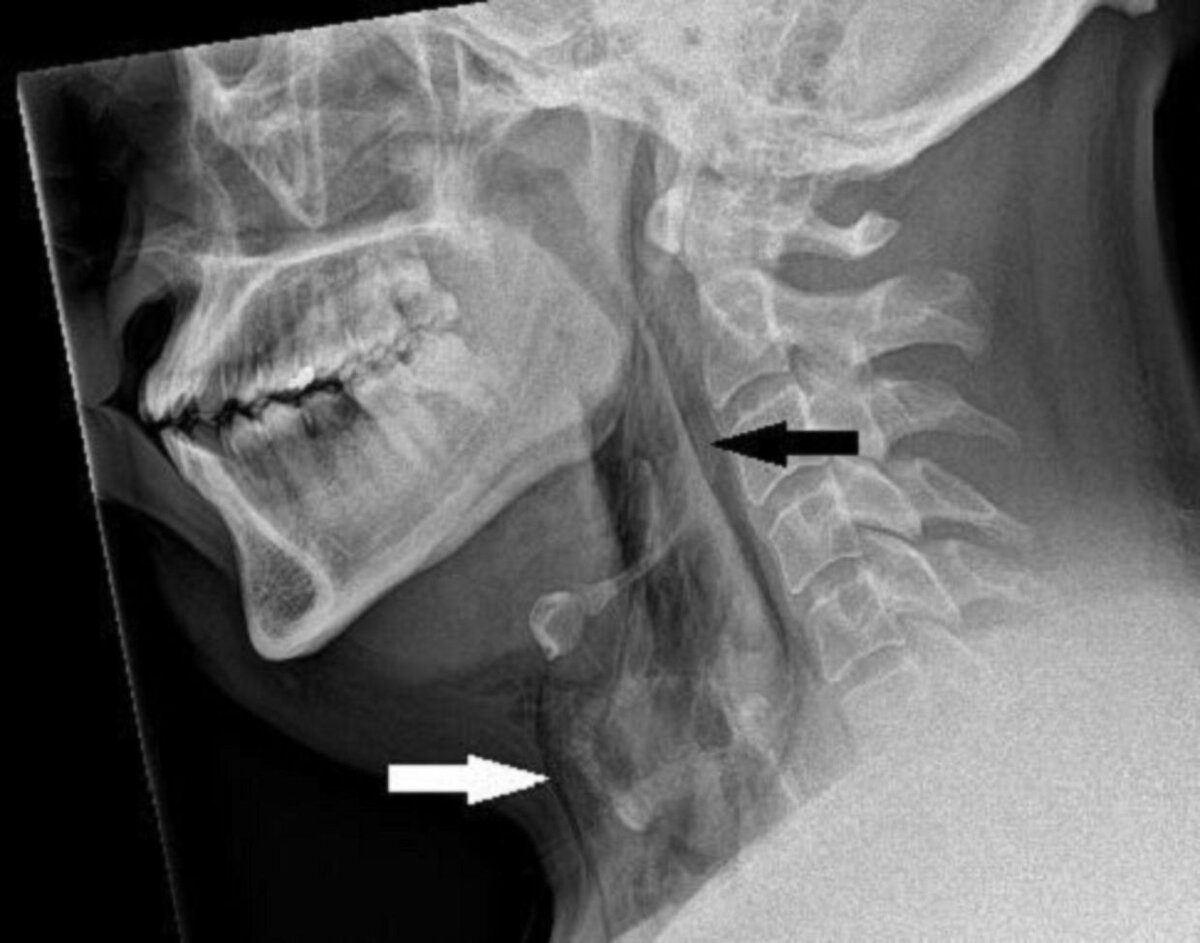

Случай с мужчиной, о котором сообщается в журнале BMJ Case Reports, - единственный известный случай, когда это вызвало разрыв горла. Когда он поступил в отделение неотложной помощи больницы, его шея опухла с обеих сторон, и он с трудом двигал ею. Рентген показал, что у него хирургическая эмфизема - когда воздух задерживается в самых глубоких тканях под кожей.

Компьютерная томография показала, что разрыв находится между третьей и четвертой костями шеи, а воздух скапливается в пространстве между легкими в груди. Врачи решили, что операция ему не нужна, но два дня наблюдали за ним в больнице, чтобы убедиться, что уровень кислорода остается стабильным.